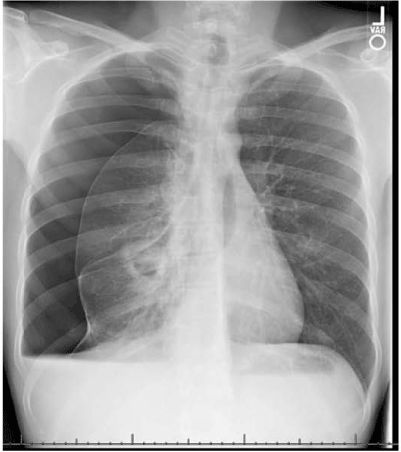

In 2018, a 46-year-old Caucasian male with medical history of hyperlipidemia and recurrent pneumonia and bronchitis, presented to the emergency department in Flagstaff, Arizona with complaints of right sided pleuritic chest pain for 5 days, with associated cough and fever with a maximum temperature of 104°F. The patient was initially evaluated at his primary care provider’s office, where he received clarithromycin for pneumonia after a chest x-ray revealed the presence of a right upper and middle lobe consolidation. His symptoms did not improve after 3 days, with worsening pleuritic pain. He admitted to productive cough with yellow sputum, and denied any weight loss, chills, night sweats, nausea, or vomiting. In the emergency department, the patient was afebrile, and oxygen saturation decreased to 86% on room air with improvement to above 90% with 2L of supplemental oxygen. Physical exam was unremarkable, and the lungs were clear to auscultation. However, subsequently became severely dyspneic with nasal flaring with removal of supplemental oxygen. Initial labs revealed hemoglobin of 15.1 g/dL, white blood cell count of 10.4 × 103/µL, platelets 208 × 103/µL, with differential of 15% lymphocytes, 75.3% neutrophils, 6.3% monocytes, 2.9% eosinophils, and 0.5% basophils. A CT angiogram of the chest ruled out pulmonary embolism and was significant for a large dense consolidation of the right upper lobe, airspace disease in the right middle and lower lobes, and right hilar mediastinal adenopathy (Figure 5). The patient was admitted to the telemetry unit for acute hypoxic respiratory failure secondary to community-acquired pneumonia with pleurisy, and empirically treated with ceftriaxone and azithromycin.

Figure 5. CT angiogram of chest: Large dense consolidation in the right upper lobe apical posterior